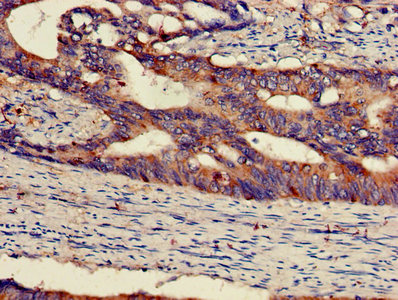

IHC image of CSB-PA013409LA01HU diluted at 1:300 and staining in paraffin-embedded human colon cancer performed on a Leica BondTM system. After dewaxing and hydration, antigen retrieval was mediated by high pressure in a citrate buffer (pH 6.0). Section was blocked with 10% normal goat serum 30min at RT. Then primary antibody (1% BSA) was incubated at 4°C overnight. The primary is detected by a biotinylated secondary antibody and visualized using an HRP conjugated SP system.